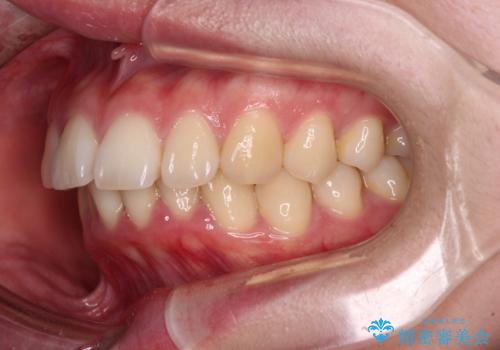

- 下唇に跡がつくほどに飛び出した上顎前歯を気にして来院された患者様です。

来院された時から4本の抜歯が必要であることを理解されていらしており、通法通り上下左右の第一小臼歯4本を抜歯し、ワイヤー装置にて矯正治療を行うこととしました。

順調に治療が進み、2年弱で想定していたとおりの仕上がりにて治療を終えることができました。